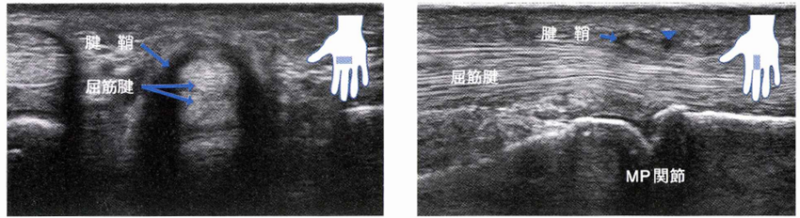

指が引っかかる感じがすると訴える場合は,ばね指を想定して診断します。また、指を動かすと痛いと訴えられる場合は、ばね指の場合には、指の付け根(A1プーリー部)上図の●部分やPIP関節(親指の場合はIP関節)●に痛みが発生します。ばね指は、母指〉中指・環指〉示指〉小指の順番に発生しやすいとされ、糖尿病・透析患者に多いとされています。

超音波短軸像:中指腱鞘(A1プーリー)の肥厚を認める 超音波長軸像:腱鞘(A1プーリー)が屈筋腱に食い込んでいる。